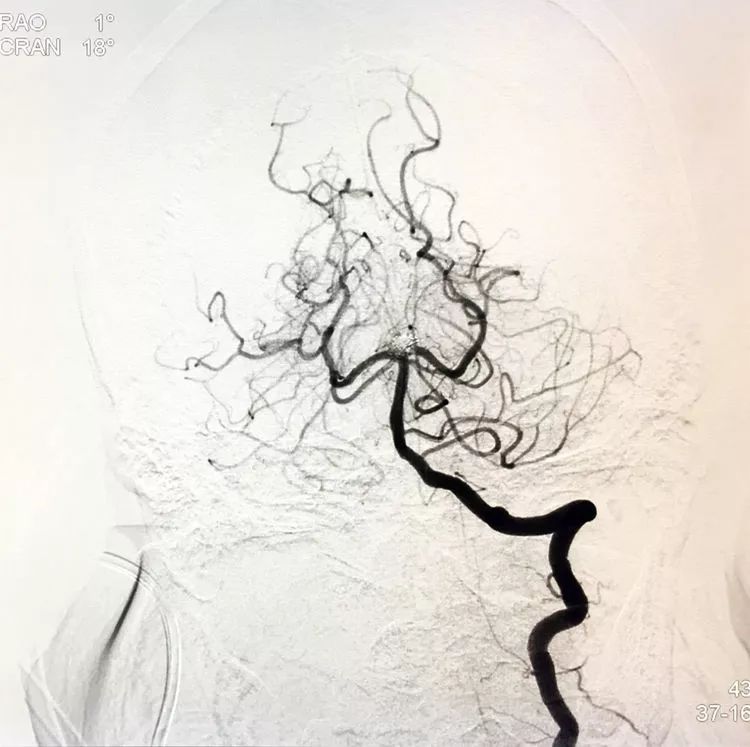

左椎动脉正位造影可以看到指向左方的子瘤。

左椎动脉工作位路图